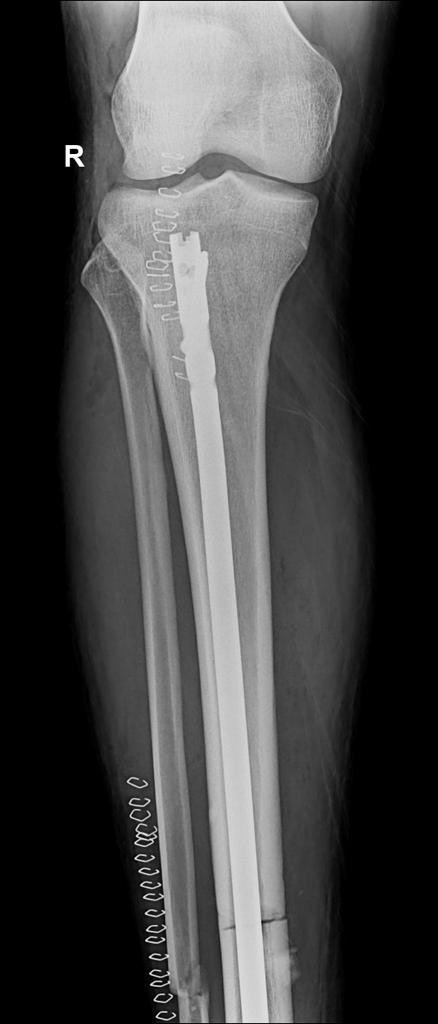

Nyuma y’imvune umunyezamu wa AS Kigali, Kimenyi Yves yagiriye ku mukino wa shampiyona wahuzaga Musanze Fc na AS Kigali, azamara amezi atandatu hanze y’ikibuga.

Kimenyi wabazwe kuwa mbere, arava mu bitaro by’Inkurunziza Orthopedic Specialized kuri uyu wa Kane tariki 2 Ugushyingo 2023.